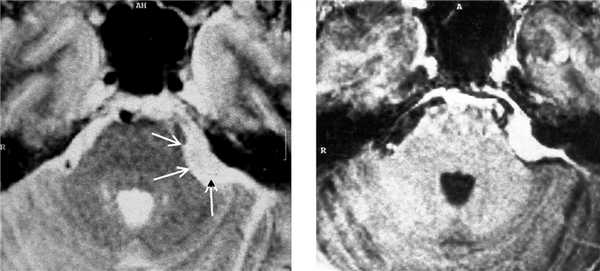

(а) Бесконтрастная КТ, аксиальный срез: у мужчины 33 лет с длительным анамнезом судорожных приступов в верхне-задней части правой теменной доли визуализируется кальцифицированное объемное образование, повторяющее ход извилин.

(б) MPT, FLAIR, аксиальный срез: у того же пациента в структуре коры визуализируется гипоинтенсивное объемное образование.

2. КТ при менингоангиоматозе:

• Бесконтрастная КТ:

о Одиночное гиперденсное, часто кальцифицированное объемное образование:

- Линейный, гиральный или узловой характер Са++

о Обнаруживаются случайно: кровоизлияния и кисты

о Масс-эффект отсутствует или не определяется

• КТ с контрастированием:

о Контрастирование низкоинтенсивное или отсутствует

(а) MPT, Т2* GRE, аксиальный срез: определяются участки «выцветания» изображения, соответствующие участкам кальцификации гирального характера.

(б) Постконтратсное Т1-ВИ, режим подавления сигнала от жира, аксиальный срез: определяется контрастное усиление объемного образования серпантинного, гирального характера.

Других областей поражения или кожных аномалий выявлено не было. На данных снимках представлен случай предполагаемого (хирургически не подтвержденного) менингоангиоматоза.